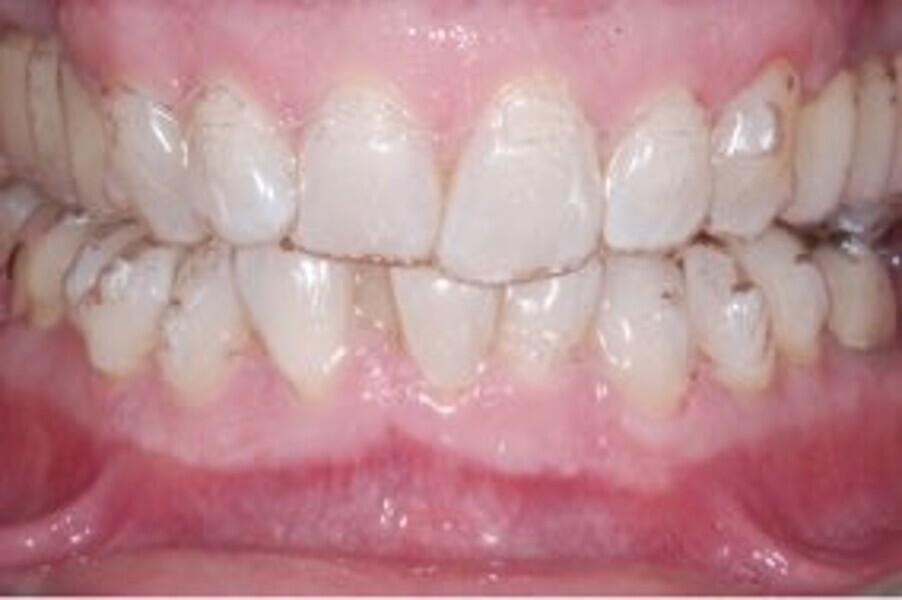

At the end of the treatment, Class I canine and molar relationships were obtained, maxillary incisor inclination was slightly increased (Ui–FH = 112°), mandibular incisor inclination (IMPA = 97.09°) was fully corrected by means of proclination and the divergency was slightly increased (SN–GoGn = 27°) because of the relative posterior extrusion and use of Class II elastics—a small variation (1°), which is interesting considering the age of the patient (Figs. 25–35). A balanced smile arc was obtained with an ideal relationship between the maxillary incisors and lower lip, and torque control of the lateral and posterior segments generated a broader smile.

At the one-year follow-up in retention (Vivera retainers with bite ramps, Align Technology), the result was stable and intercuspation was improved (Figs. 38–42).